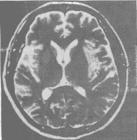

4. 影像學檢查: 頭顱CT可正常,也可見一側或雙側顳葉、海馬及邊緣系統局灶性低密度區,若其中出現點狀高密度提示有出血性壞死,更支持診斷。嚴重者可有腦室受壓、中線移位等占位效應。在早期MRI T2加權像可見到顳葉中、下部,向上延伸島葉及額葉底面有周邊清晰的高密度區。MRI優於CT,尤其可發現早期病灶。

單純皰疹病毒性腦炎(5)頭顱CT或MRI發現顳葉局灶性出血性腦軟化灶;